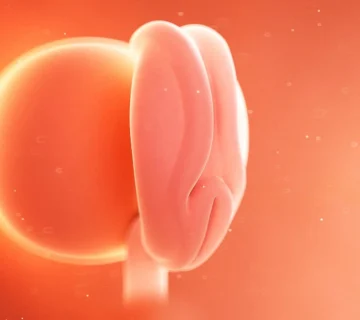

در همین زمان، سایر اندامهای بدن نیز در حال شکلگیری هستند. مغز نوزاد وارد مرحلهای میشود که به دو نیمکره تقسیم میگردد و دستگاه تنفسی به صورت شیارهایی در پشت صورت ظاهر میشود. با گذشت روزها، قسمتهای پایینتنه جنین رشد بیشتری پیدا میکنند و ریهها طی ۲۳ مرحلهی زمانی بهتدریج تکامل مییابند.

رشد مغز و سیستم عصبی

در این هفته، سیستم عصبی مرکزی جنین (مغز و نخاع) در حال تشکیل است. لولهی عصبی که از پشت جنین امتداد دارد، بهتدریج بسته میشود و سلولهای عصبی شروع به تقسیم و تمایز میکنند. این فرآیند، آغاز رشد مغز و اعصاب است — همان بخشی که در آینده مسئول تفکر، احساس و حرکت نوزاد خواهد بود.

در این مرحله، دستها و پاهای جنین به شکل جوانههای کوچک و پرهدار ظاهر میشوند. سر جنین بزرگتر از سایر بخشهای بدن است، زیرا رشد مغز سریعتر از سایر اندامها انجام میشود. چشمها، گوشها و دهان نیز در قالب نقاط تیرهی کوچکی در حال شکلگیری هستند.